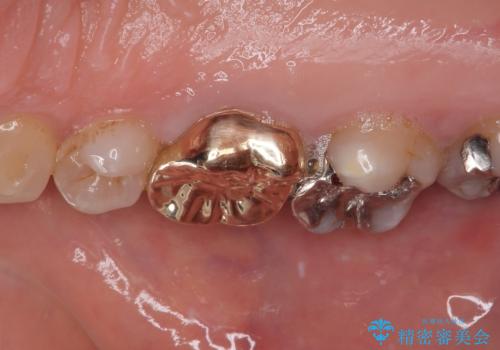

銀歯の下のむし歯 ゴールドクラウンによる補綴治療

咬み合わせが非常に強く、見た目よりも機能と安定性を重視したいとのことで、PGAクラウン(白金加金合金クラウン)にて補綴する治療計画となりました。

PGAクラウンにしたことで咬み心地に全く違和感がなく、気にされていた審美面も、奥歯でありそれほど目立たないこともありますが、白金加金の色を気に入っていただけたので、患者様には大変満足していただけました。